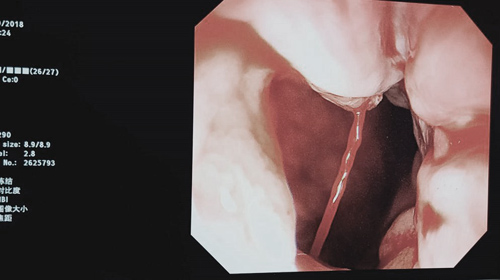

急性消化道出血是消化系统疾病中常见的并发症,其中以食管或胃底静脉曲张破裂出血尤为棘手,严重时常危及生命,准确的诊断和对治疗效果的判断至关重要。近日来,分别有三例患者均以大量呕血及解黑便入院,入院时均已失血性休克。经入院辅助检查及综合患者病情诊断为肝硬化伴食管胃底静脉曲破裂出血,消化内科专家经过充分讨论决定为患者行内镜下食管胃底静脉曲张精准断流术(ESVD)治疗。经过充分术前评估和准备,三次均由蔡长春主任领导、消化内科肝病亚学科副组长胡敏副主任医师行急诊ESVD治疗,在精准治疗思想的指导下,高效完成内镜下血管断流,迅速止血挽救病人生命。目前三例患者均已平稳。

内镜下食管胃底静脉曲张精准断流术(ESVD)是近来在国内兴起的一种有效的门脉高压食管胃底静脉曲张的内镜下治疗方法,即在内镜下寻找静脉曲张来源血管,并将组织胶用注射针多点少量精准注射入来源血管将其阻断,可以达到即时止血的效果,并最大程度的预防出血,达到食管胃底静脉曲张一次性消除的目的。该项技术较传统的内镜下食管胃底静脉曲张治疗方法具有零创伤、痛苦小、见效快、疗效好、费用低、术后并发症少等优点,是目前业界专家公认的食管胃底静脉曲张最佳治疗方案。临床医学院/附属医院消化内科于近期成立了肝病亚学科,重点发展方向为内镜下ESVD术治疗肝硬化伴胃底静脉曲张破裂出血,并已派遣胡敏副主任医师赴地坛医院进修学习。目前使用ESVD技术共成功施治30余例此类患者,无一例并发症发生,社会效应显著。